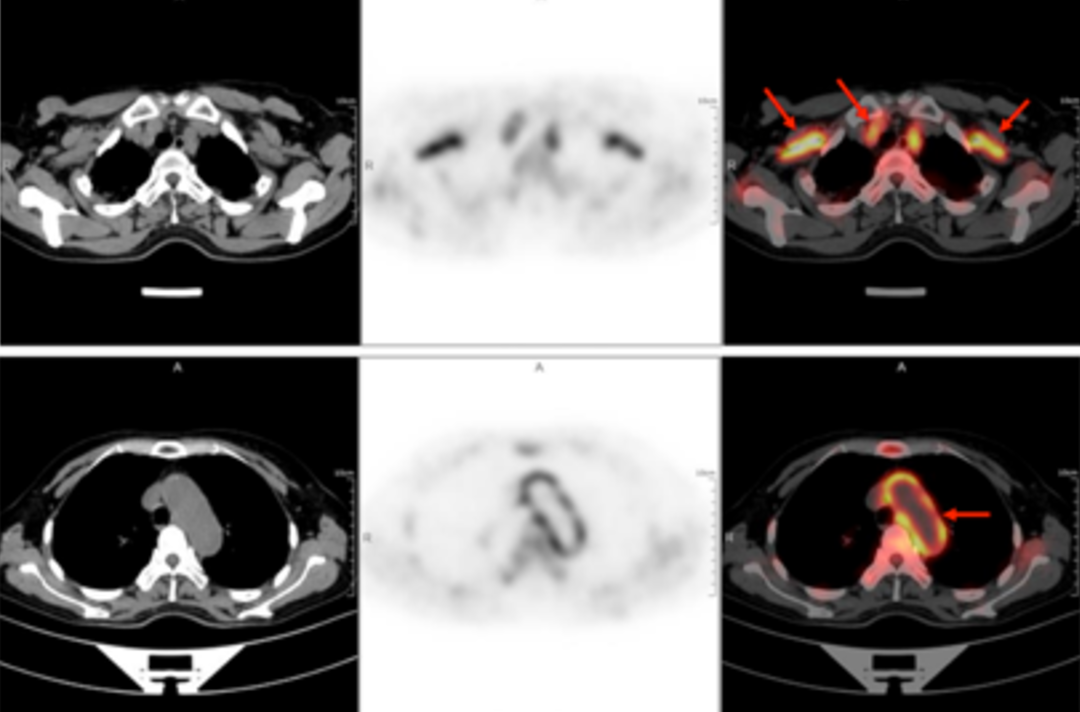

A 58-year-old women went to the hospital for intermittent fever for more than 40 days. Her highest body temperature was 38.9℃. Other symptoms included fatigue and shoulder joint pain which were especially acute in the afternoon and at night without cold, chills, sputum, hemoptysis, chest pain, chest tightness and shortness of breath. After two weeks of intravenous administration of "cephalosporin antibiotics" there was no improvement, and intermittent fever continued. The outpatient clinics noted the patient had "fever of unknown origin." There were no obvious diagnostic features upon physical examination. The results of a routine blood test were as follows: erythrocyte sedimentation rate in the first hour: 72mm; high-sensitivity C-reactive protein: 204. 20mg/l. Then, the patient had a whole-body F-FDG PET-CT examination to find the cause of the fever of unknown origin.

In the PET/CT images, wall thickening with increased glucose metabolism occurred in several parts of the body (bilateral internal carotid artery, common carotid artery, brachiocephalic trunk, bilateral subclavian and axillary arteries, thoracic aorta, abdominal aorta, bilateral common iliac artery, internal iliac artery, external iliac artery and femoral artery), which was considered to be caused by inflammatory changes. Combined with the patient’s medical history, clinical symptoms, examination and imaging findings, she was diagnosed with T.A. After standardized anti-inflammation treatment, her body temperature dropped and her condition improved.